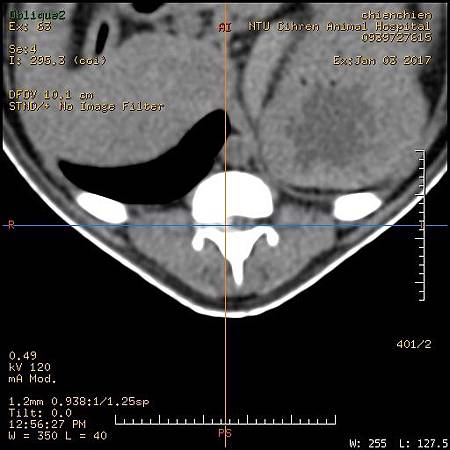

1. 臘腸 IVDD椎間盤突出

3. 臘腸IVDD 椎間盤突出